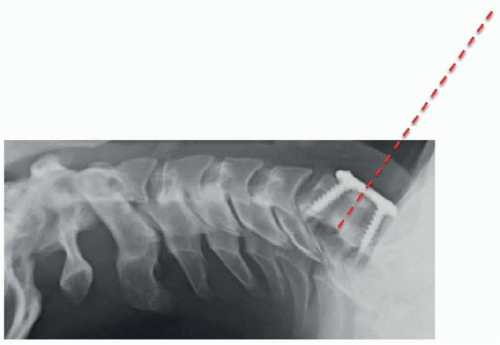

A 58-year-old woman with 2 years of progressive cervical myelopathy, manifesting as hand dysfunction and gait imbalance. There is overall mild cervical kyphosis and a spondylolisthesis at C3-4. Magnetic resonance imaging (MRI) demonstrates mild-to-moderate cord and/or compression from C4-7 (Figure 1-1).

For procedures involving C4 and above, nasotracheal intubation can be considered in select patients to facilitate access by allowing dental apposition. The need for this can be assessed by examining the position of the mandible with respect to the line of sight to the desired disk space on a preoperative lateral x-ray.

Approximate location of incision can also be estimated on the basis of distance between mandible and sternum on preoperative lateral x-ray (Figure 1-7).